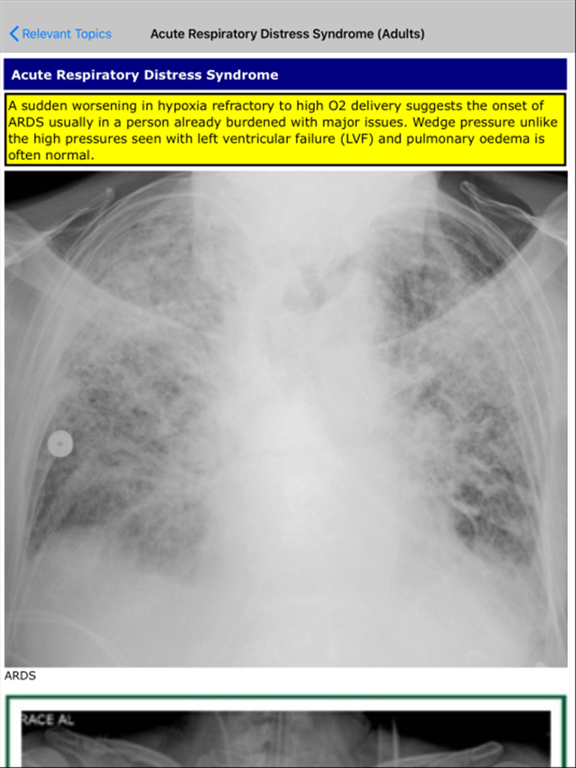

Access clinical notes on 3,000+ concise topics for exams and ward rounds. Search using title or advanced super-search for rapid information retrieval. Includes facts for rare terms and supports students and practicing doctors.

Makindo Medical Notes gives you instant access to 3,000+ concise, clinically focused topics—perfect for ward rounds, clinic, MCQs, and exam prep (Finals, MRCP, USMLE). Use quick Title Search or the powerful Super-Search to scan 2,000+ pages of facts and find exactly what you need in seconds—even for rare terms. Built for medical students, doctors who want trusted, high-yield educational notes at their fingertips—on the ward, on the commute, or between patients.